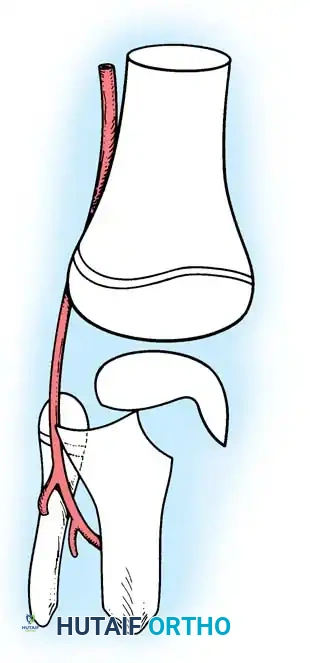

Fractures of the proximal tibial epiphysis demand heightened vigilance due to their intimate anatomical relationship with the popliteal artery.

In 1965, Aitken made two seminal observations regarding these injuries:

2. Vascular Proximity: The popliteal artery is firmly tethered posteriorly by the fibrous arch of the soleus muscle. When the proximal tibial shaft is displaced posteriorly in Salter-Harris Type I and II fractures, the artery is stretched over the sharp metaphyseal ridge, leading to intimal tearing, thrombosis, or complete transection.

Fig. 33-173: Salter-Harris type I and II fractures with posterior displacement of the tibial shaft may severely injure the popliteal artery.

Wozasek et al. reported that 13% of patients with proximal tibial physeal injuries exhibited peripheral ischemia. Immediate vascular assessment (Ankle-Brachial Index, Doppler ultrasound, or CT angiography) is mandatory for any displaced proximal tibial fracture.